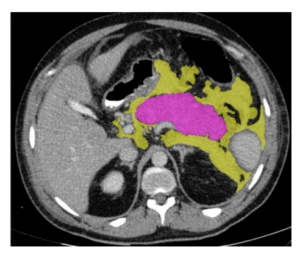

Large-scale multi-center CT and MRI segmentation of pancreas with deep learning (PanSegNet)

Authors: Zheyuan Zhang, Elif Keles, Gorkem Durak, Yavuz Taktak, Onkar Susladkar, Vandan Gorade, Debesh Jha, Asli C. Ormeci, Alpay Medetalibeyoglu, Lanhong Yao, Bin Wang, Ilkin Sevgi Isler, Linkai Peng, Hongyi Pan, Camila Lopes Vendrami, Amir Bourhani, Yury Velichko, Boqing Gong, Concetto Spampinato, Ayis Pyrros, Pallavi Tiwari, Derk C.F. Klatte, Megan Engels, Sanne Hoogenboom, Candice W. Bolan, Emil Agarunov, Nassier Harfouch, Chenchan Huang, Marco J. Bruno, Ivo Schoots, Rajesh N. Keswani, Frank H. Miller, Tamas Gonda, Cemal Yazici, Temel Tirkes, Baris Turkbey, Michael B. Wallace, Ulas Bagci

MEDICAL IMAGE ANALYSIS - 2025

Publication Year: 2025